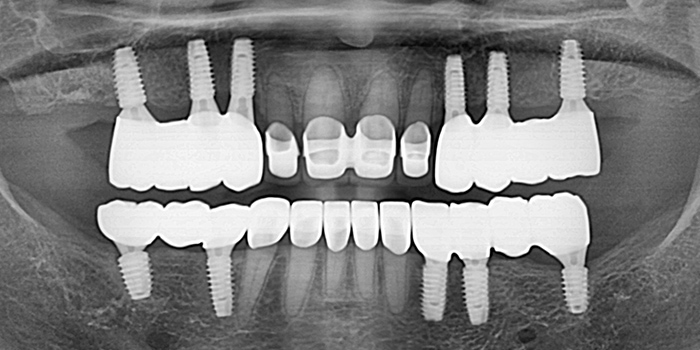

05 60대 남성, 기존 임플란트 부작용으로 재수술, 치료기간 6개월